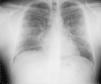

Varón de 26 años, sin antecedentes patológicos, culturista profesional, que consultó por disnea de esfuerzo progresiva de grado III y tos seca de 24h de evolución tras administrarse una primera dosis intramuscular de metenolona (300mg). En el examen físico estaba afebril, con presión arterial, frecuencia cardíaca y respiratoria normales. Se objetivó murmullo vesicular conservado, sin ruidos patológicos. El resto era normal. La analítica mostraba 18.200 leucocitos/μl (un 85% neutrófilos y un 0,4% eosinófilos), y los resultados de la gasometría arterial (fracción inspiratoria de oxígeno de 0,21) fueron los siguientes: pH de 7,45, presión arterial de anhídrido carbónico de 35mmHg, presión arterial de oxígeno de 60mmHg y HCO3 de 25mmol/l; el resto de los parámetros bioquímicos y de coagulación fueron normales. La radiología simple de tórax mostró un patrón alveolointersticial nodular, bilateral. Se inició antibioterapia con levofloxacino y se interrumpió la metenolona. La tomografía computarizada de tórax al ingresar el paciente reveló áreas parcheadas de neumonitis en vidrio deslustrado, de predominio periférico y en campos superiores. La tinción de Ziehl-Neelsen, el cultivo de Löwenstein-Jensen, la antigenuria para Legionella pneumoniae y Streptococcus pneumoniae, así como la serología para neumonías atípicas (Mycoplasma pneumoniae, L. pneumoniae, Coxiella burnetii, Chlamydia pneumoniae y virus respiratorio sincitial), resultaron negativos. La espirometría mostraba: capacidad vital forzada (FVC) de 4,76l (79%), volumen espiratorio forzado en el primer segundo (FEV1) de 4,45l (93%) y FEV1/FVC del 93%. La capacidad de transferencia de monóxido de carbono (TLCO) fue de 10,17mmol/min/kPa (75%), y el valor corregido por el volumen alveolar (TLCO/VA), de 1,81mmol/min/kPa/l (86%). A las 48h del ingreso se suspendió el tratamiento antibiótico. El paciente experimentó mejoría clínica y resolución radiográfica al séptimo día, con una saturación de oxígeno por pulsioximetría (respirando aire ambiente) del 97%. Al cabo de un mes, la radiografía de tórax (fig. 1) continuaba sin anomalías y se observó una mejoría funcional: FVC de 5,45l (91%), FEV1 de 5,06l (106%), FEV1/FVC del 92%. La TLCO era de 15,41mmol/min/kPa (114%) y la TLCO/VA de 2,42mmol/min/kPa/l (115%).